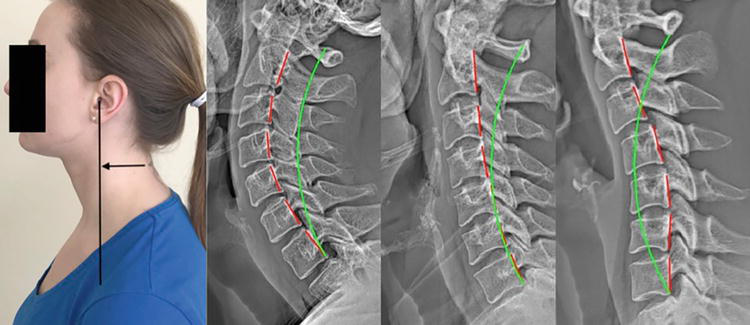

Various examples of structural abnormalities associated with forward head posture as seen on digital radiography (x-ray), green line represents normal alignment, red line represents patient's alignment.

Images demonstrating Structural Abnormalities in red with green line showing normal spinal reference position for more explanation please read from source:

E. Harrison, D. and P. A. Oakley (2022). An Introduction to Chiropractic BioPhysics® (CBP®) Technique: A Full Spine Rehabilitation Approach to Reducing Spine Deformities, IntechOpen.